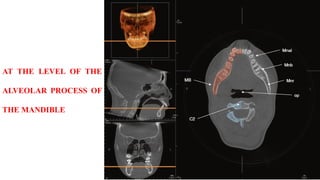

AT THE LEVEL OF THE

MANDIBULAR FORAMEN

ALVEOLAR PROCESS OF

THE MANDIBLE

AT THE LEVELOF THE ALVEOLAR PROCESS OF THE MANDIBLE